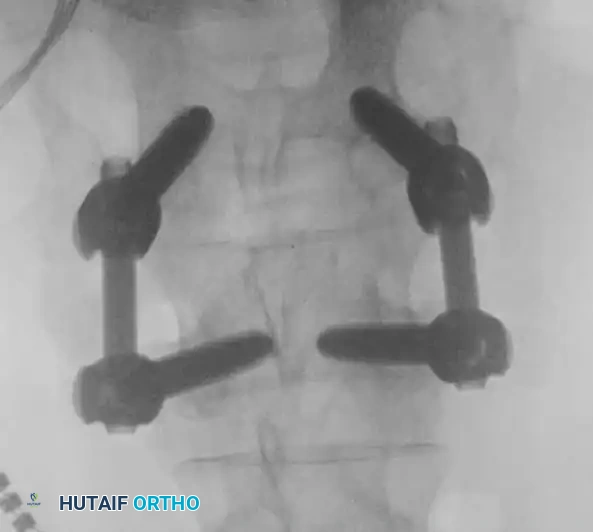

5. Pedicle Screw Instrumentation and Fluoroscopic Verification

• Pedicle screws are placed bilaterally into the cephalad and caudal vertebrae. The entry point is typically at the intersection of the pars interarticularis, the superior articular facet, and the transverse process.

• The pedicles are cannulated with a gearshift probe, palpated with a ball-tip feeler to ensure no cortical breaches, tapped, and the screws are inserted.

• Intraoperative fluoroscopy is absolutely critical during this phase to confirm trajectory and depth.

Image

Alternative AP fluoroscopic view confirming bilateral symmetry and appropriate convergence of the pedicle screws, ensuring they do not breach the medial pedicle wall into the spinal canal.

• Once screw placement is confirmed, titanium or cobalt-chrome rods are contoured to match the patient's natural lumbar lordosis and secured to the screw heads with set screws.

• Compression is applied across the construct to load the interbody cage, adhering to Wolff's Law to promote osteogenesis.